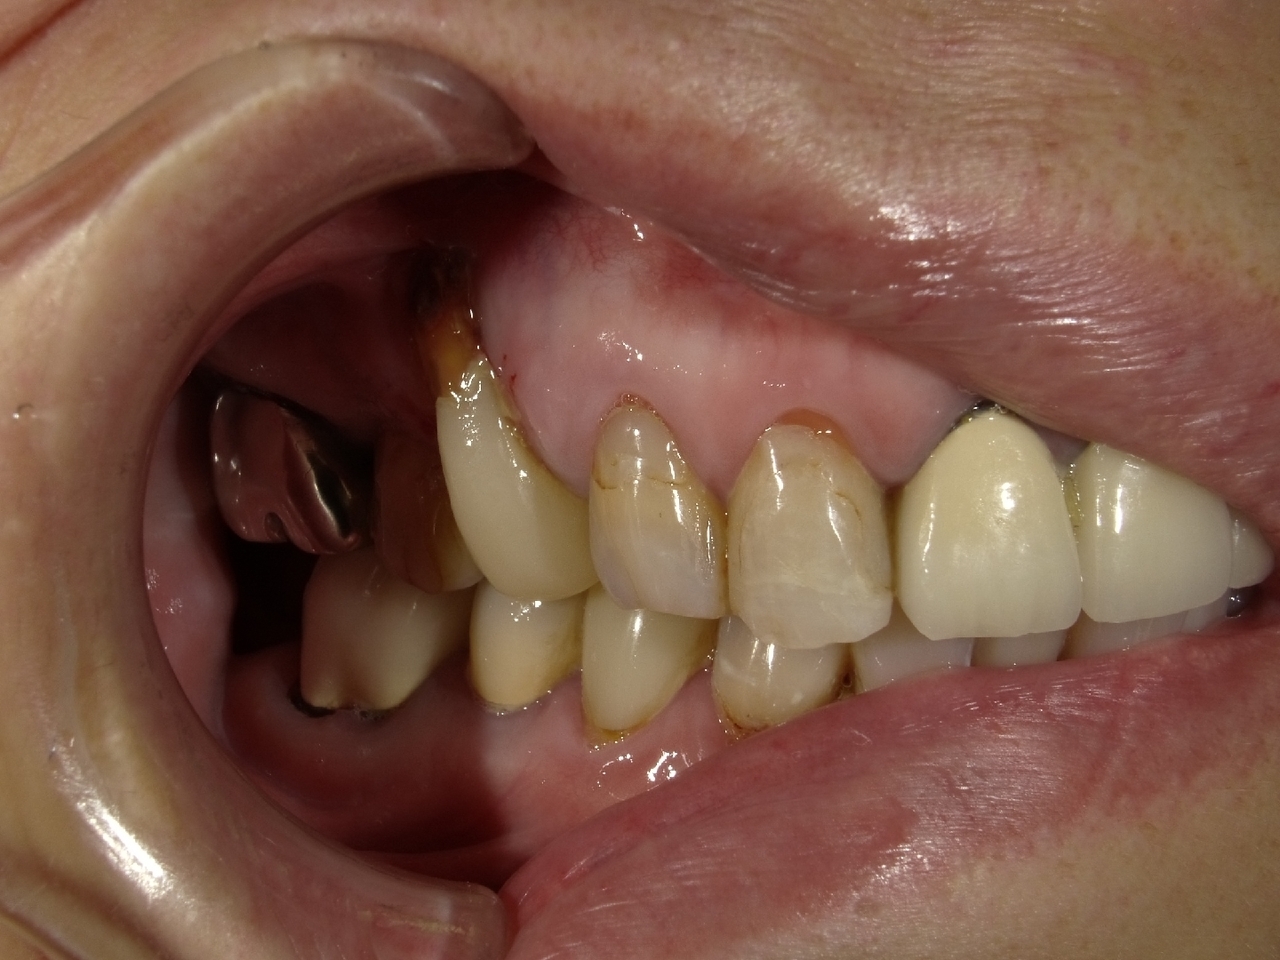

2.右上2番の前歯が、虫歯で折れてしまって、インプラント埋入当日に抜歯とインプラント埋入、仮歯まで装着して、2か月半で最終的な歯を入れたケース

Before

K・Y 様 女性 50代

右上の2番3番がカリエスと食いしばりにより、破折したため、インプラント治療を希望

治療法としては、右上2番3番ともに、保存は、難しそうだったっが、患者様の希望もあり、右上3番は、歯を保存して、保険治療の前歯部のCADCAM冠で、どうしても残すことが無理であった右上2に関しては、インプラント手術、当日に抜歯をおこない、インプラント埋入をおこない、仮歯まで装着して、硬いものは、避けてもらうことを条件に食事ができる状態と歯がある状態で手術を終えました。その後、で2か月後にデジタル印象をおこない、2か月半で最終的なジルコニアの歯を入れ、治療を終えることができました。

治療の期間・回数:約2か月半、5回

治療の価格:404000円(税込)

治療費の内訳:インプラント基本料(フィックスチャー(ストローマン BLTインプラント使用)及び手術費用、投薬費用、レントゲン費用、インプラント上部費用(アバットメントおよびジルコニア)クラウンの費用用)360000円(税込み)オプション費用:抜歯即時埋入即時負荷加算(人口コツ費用を含む) 費用 44000円(税込み)

治療のリスクや副作用:手術後に、痛みや腫れ、出血、合併症などを引き起こす可能性があります。噛む感覚がご自身の歯と異なる場合があります。見た目がご自身の歯と異なる場合があります。手術後にメインテナンスを継続しないと、インプラントが抜け落ちる可能性があります。